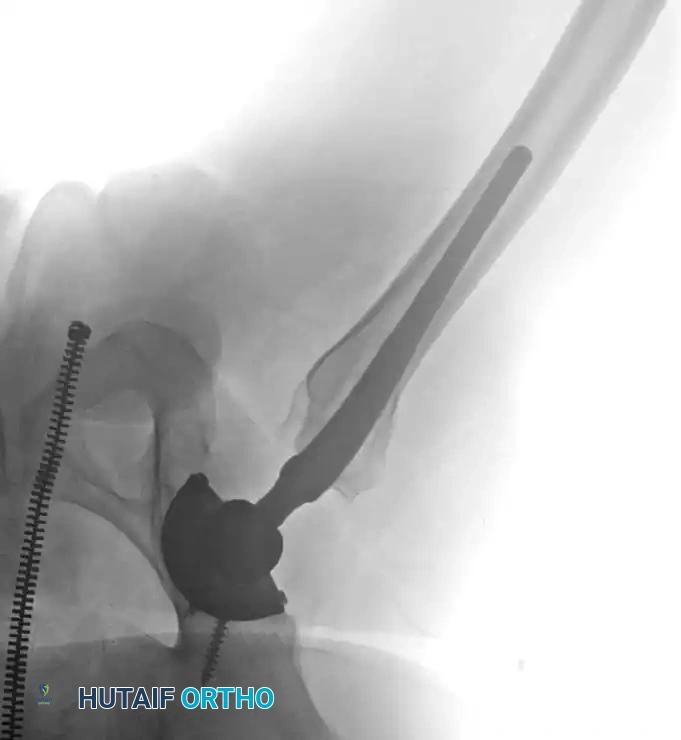

The following radiographic and illustrative figures detail the preoperative planning, biomechanical axes, and intraoperative fixation strategies critical for successful osteotomies around the knee.

Intraoperative fluoroscopy is utilized to confirm the osteotomy trajectory. Guide pins are placed parallel to the joint line, ensuring the hinge point remains intact to provide intrinsic stability to the osteotomy site.

Rigid internal fixation is achieved using anatomically contoured locking plates. In opening wedge osteotomies, the plate acts as a buttress to maintain the correction angle while the osteotomy heals.

Careful soft tissue management is required. In medial opening wedge HTO, the superficial medial collateral ligament (sMCL) must be partially released distally to allow the osteotomy to open without increasing medial compartment contact pressures.

For distal femoral osteotomies, the plate is typically applied to the medial or lateral cortex depending on the wedge orientation. The fixation must be robust enough to withstand the significant bending moments present at the distal femur.